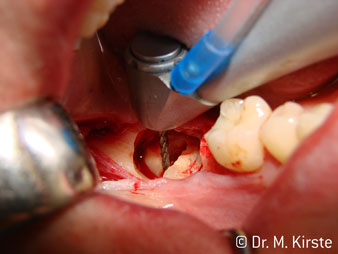

45° açılı angldruva geniş avantaj yelpazesi sebebiyle özellikle seçildi. Bu enstrümanın geliştirilme nedeni olan cerrah meslektaşlarım angldruvaların kısıtlı alanlardaki çalışma yeteneğini yakında takdir edeceklerdir. Özellikle gömük diş çekimlerinde (res. 2) yumuşak dokunun yanak bölgesine doğru yarılmasına gerek kalmaz(res. 3). Angldruvanın kafa dizaynı sayesinde retromolar bölgede hızlı ve güvenli çalışma sağlar.

Angldruva kafası içindeki profesyonel tasarımlı dişliler frezin sessiz çalışmasını garanti eder; kök separasyonu yapılırken atravmatik operasyona olanak verir. (res. 4-9).